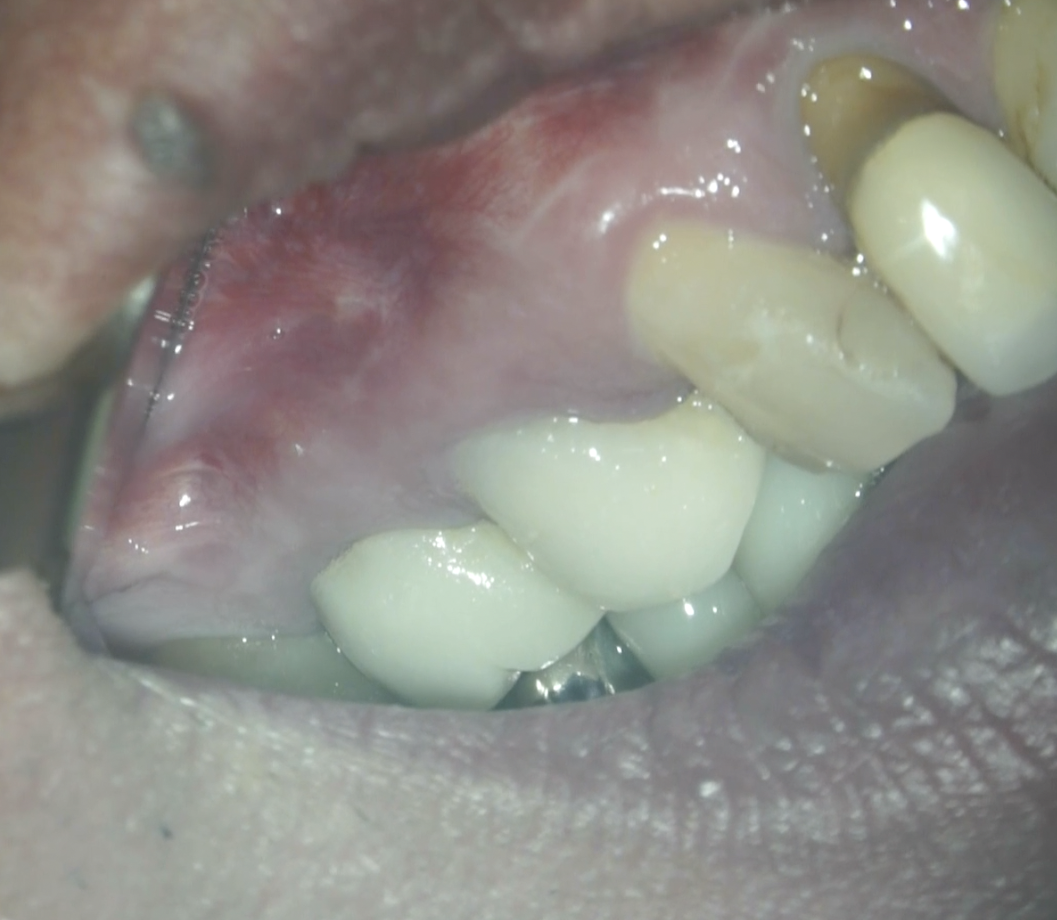

最後に縫合した。

この後、経過を追うまで1年,間を開けた。

#3 MB Apicoectomy 1yr recall(2026.3.19)

歯槽骨の欠損、Sinus tract, 臨床症状は消失した。

最終補綴もOKで、経過観察も終診とさせていただいた。

長きに渡りお疲れ様でした。